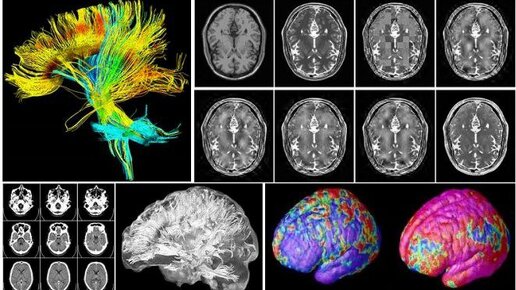

Я провел несколько дней, изучая сотни научных статей на английском языке, посвященных медитации. По результатам этой кропотливой работы я предлагаю Вам концентрат - выжимку из пары десятков наиболее интересных научных исследований в области медитации. "меняет структуру мозга, увеличивает серое вещество, улучшает память и концентрацию, эффективно лечит депрессию, стресс, зависимости, панические атаки и тревожные расстройства, повышает иммунитет, понижает артериальное давление, снижает риск инфаркта, развивает сострадание и эмпатию и т...